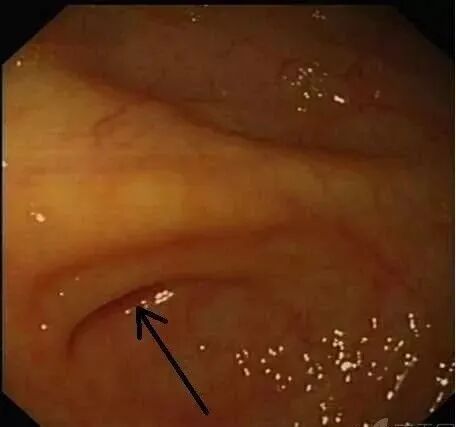

正常的阑尾开口部都被Gerlach’s瓣覆盖(如图,双箭头示Gerlach’s瓣);

通过内镜前端的透明帽的帮助下,推开Gerlach’s瓣(黄箭头),并进行阑尾腔插管。